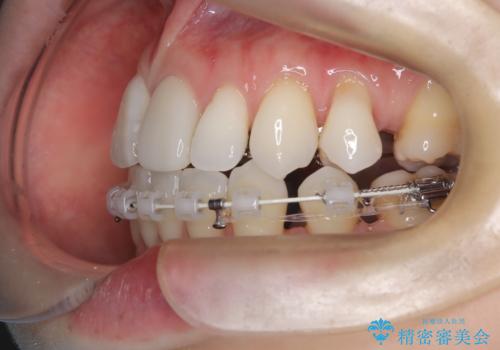

- 患者様は、歯並びの乱れ(叢生)を整えたいが、前歯の突出感は気にならないとのことで来院されました。診察の結果、全体的な歯列のスペース不足により抜歯が必要と判断。しかし、前歯を大きく下げる必要はなかったため、小臼歯の中でも5番(第二小臼歯)を抜歯する治療計画を立てました。装置は、上顎が舌側(リンガル)、下顎が表側(審美ワイヤー)のハーフリンガル矯正を採用し、目立ちにくさと効率的な歯の移動を両立しました。

抜歯によって歯を並べるためのスペースを確保。その後、ハーフリンガル矯正を用いて、上顎は舌側から、下顎は目立ちにくいワイヤーで歯を誘導し、歯列全体を整えました。治療期間を通じて、噛み合わせのバランスも改善し、機能的にも審美的にも理想的な仕上がりとなりました。患者様からは「目立たずに矯正でき、きれいな歯並びになって嬉しい」とご満足いただきました。